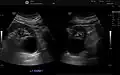

-

Renal ultrasonography of a simple renal cyst with posterior enhancement. -

Renal cyst as seen on abdominal ultrasound -